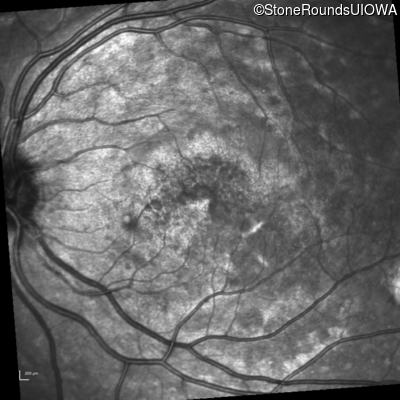

Infrared Fundus Photograph - Left - 20/25 -3 sc

Exemplar